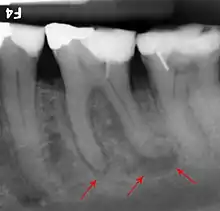

The inferior alveolar nerve (IAN), a branch of the trigeminal nerve (cranial nerve V), is a nerve that runs through the mandible (lower jaw) and supplies sensation to all the lower teeth, the lip and the chin. The lower teeth, and in particular the lower wisdom teeth, can therefore be in close proximity to this nerve. Damage to the inferior alveolar nerve is a risk of lower wisdom tooth removal (and other surgical procedures in the mandible).[20] This means there is a risk of temporary or permanent numbness or altered sensation to the lip +/- chin on the side the surgery is taking place. Therefore, in order to assess this risk and inform the patient, the position of the inferior alveolar nerve in relation to a lower wisdom tooth needs to be assessed radiographically prior to extraction.[20]

The proximity of the root to the canal can be assessed radiographically and there are several factors which can indicate high risk of nerve damage:[21]

- Darkening of the tooth root where it crosses the canal[21]

- Deviation of the canal[21]

- Narrowing of the roots[21]

- Loss of the lamina dura of the canal[21]

- Juxta apical area: a radiolucency associated with the root of the tooth which is not caused by periapical infection[21]